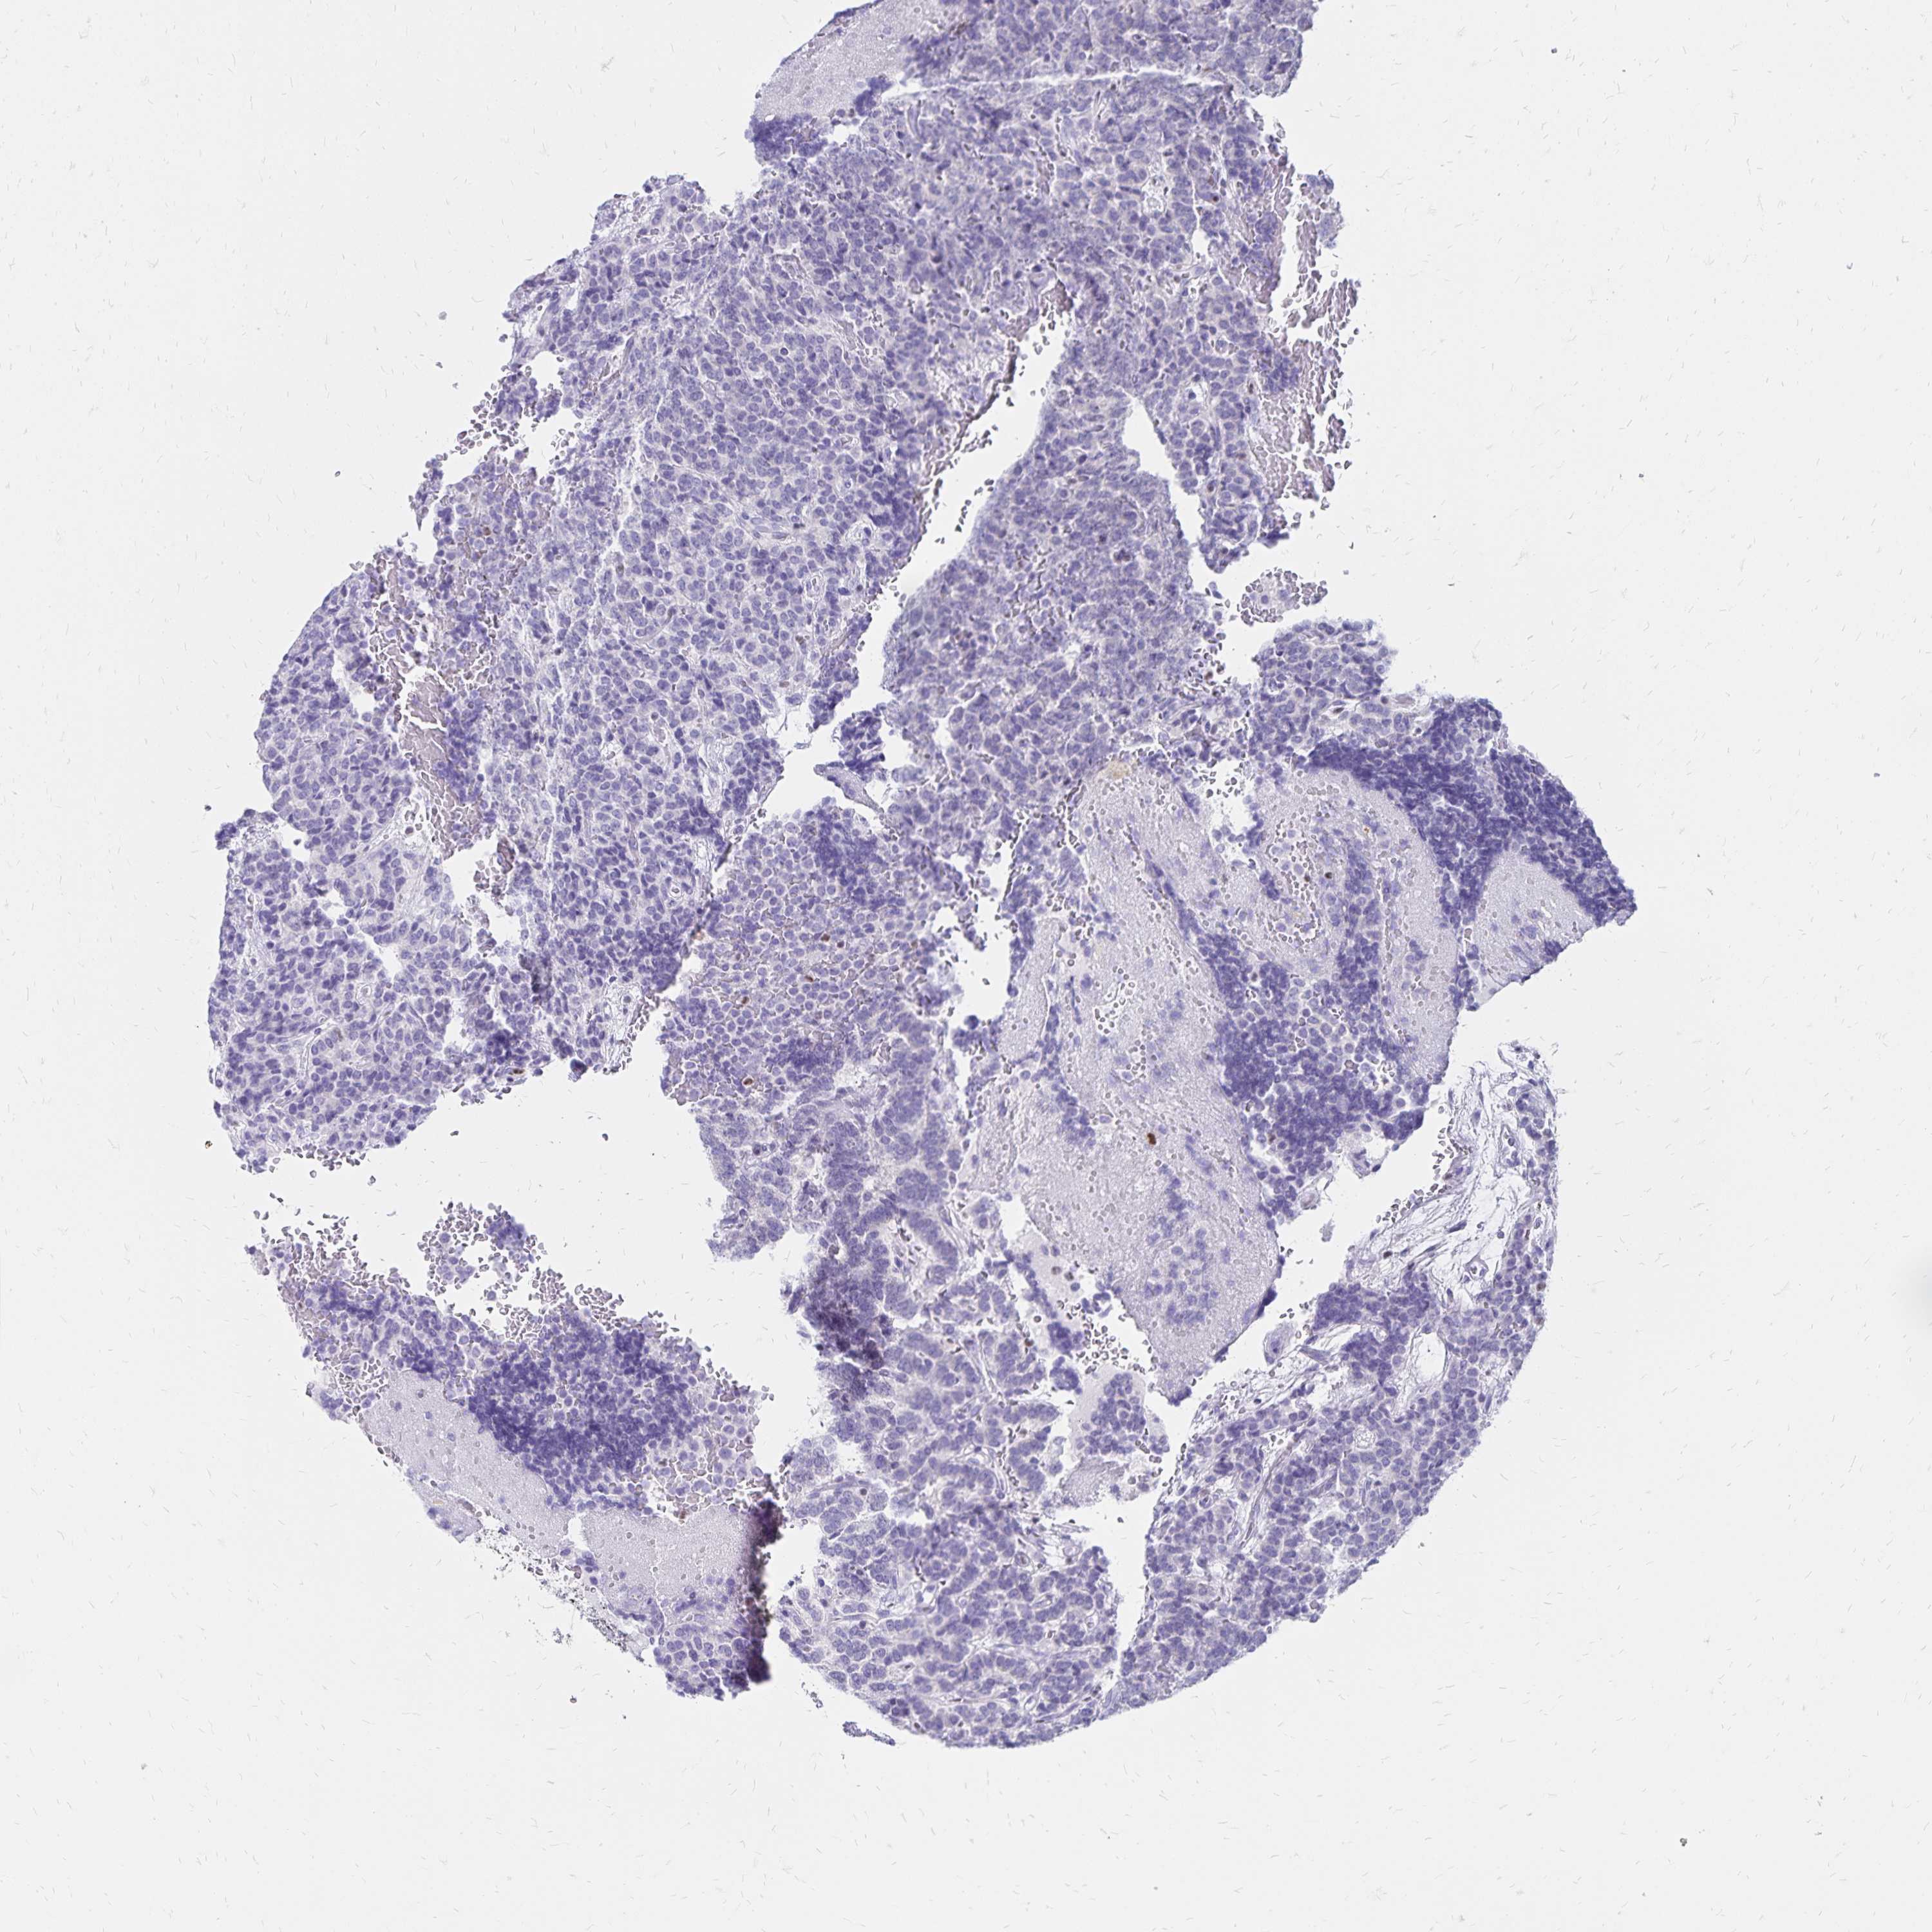

CARCINOID - Protein expressioni

A mouse-over function shows sample information and annotation data. Click on an image to view it in a full screen mode. Samples can be filtered based on level of antibody staining by selecting one or several of the following categories: high, medium, low and not detected. The assay and annotation is described here.

Each image is clickable and will lead to virtual microscopy that enables deeper exploration of all samples and also displays staining intensity scores, fraction scores and subcellular localization as well as patient and tissue information for each sample.

Antibody HPA035221

Carcinoid, malignant, NOS